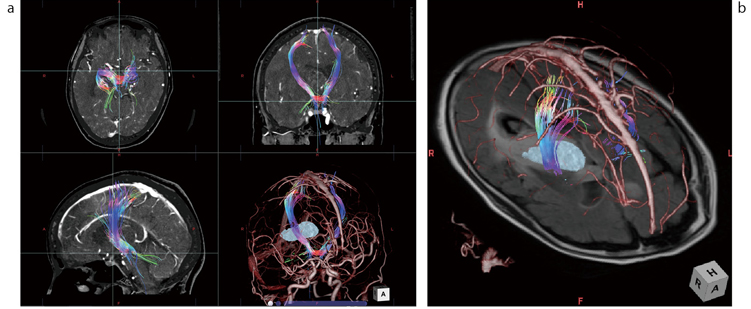

症例2(錐体路症例)

右の視床から放線冠レベルにおよぶグリオーマ症例の錐体路のトラクトグラフィー。ziostation2では他のモダリティのデータとの融合も容易である。本例ではその有用性は必ずしも高くないが、動静脈(CTAによる)と錐体路が同時に描出されている(aの右下、b)。